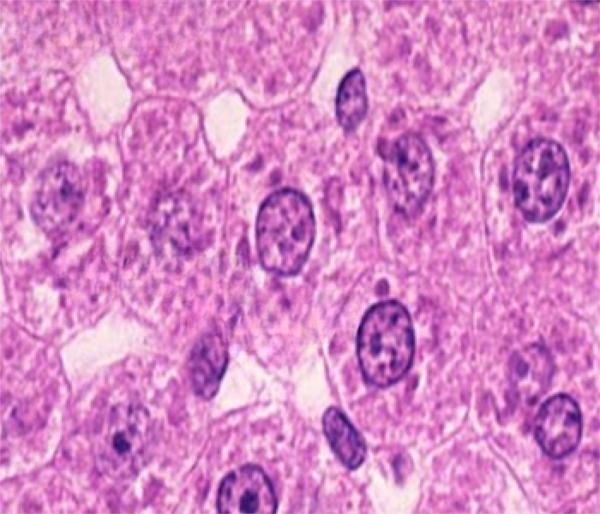

Check the listing for details. ABGIL Cytology Microscopic Slides. Condition: New. Listed at 100.00 USD. ABGIL permanent micro prepared slides differentially double or triple stained showing all the minors details. The slides are prepared by technical staff in our well equipped laboratory. microscopes slides:-.